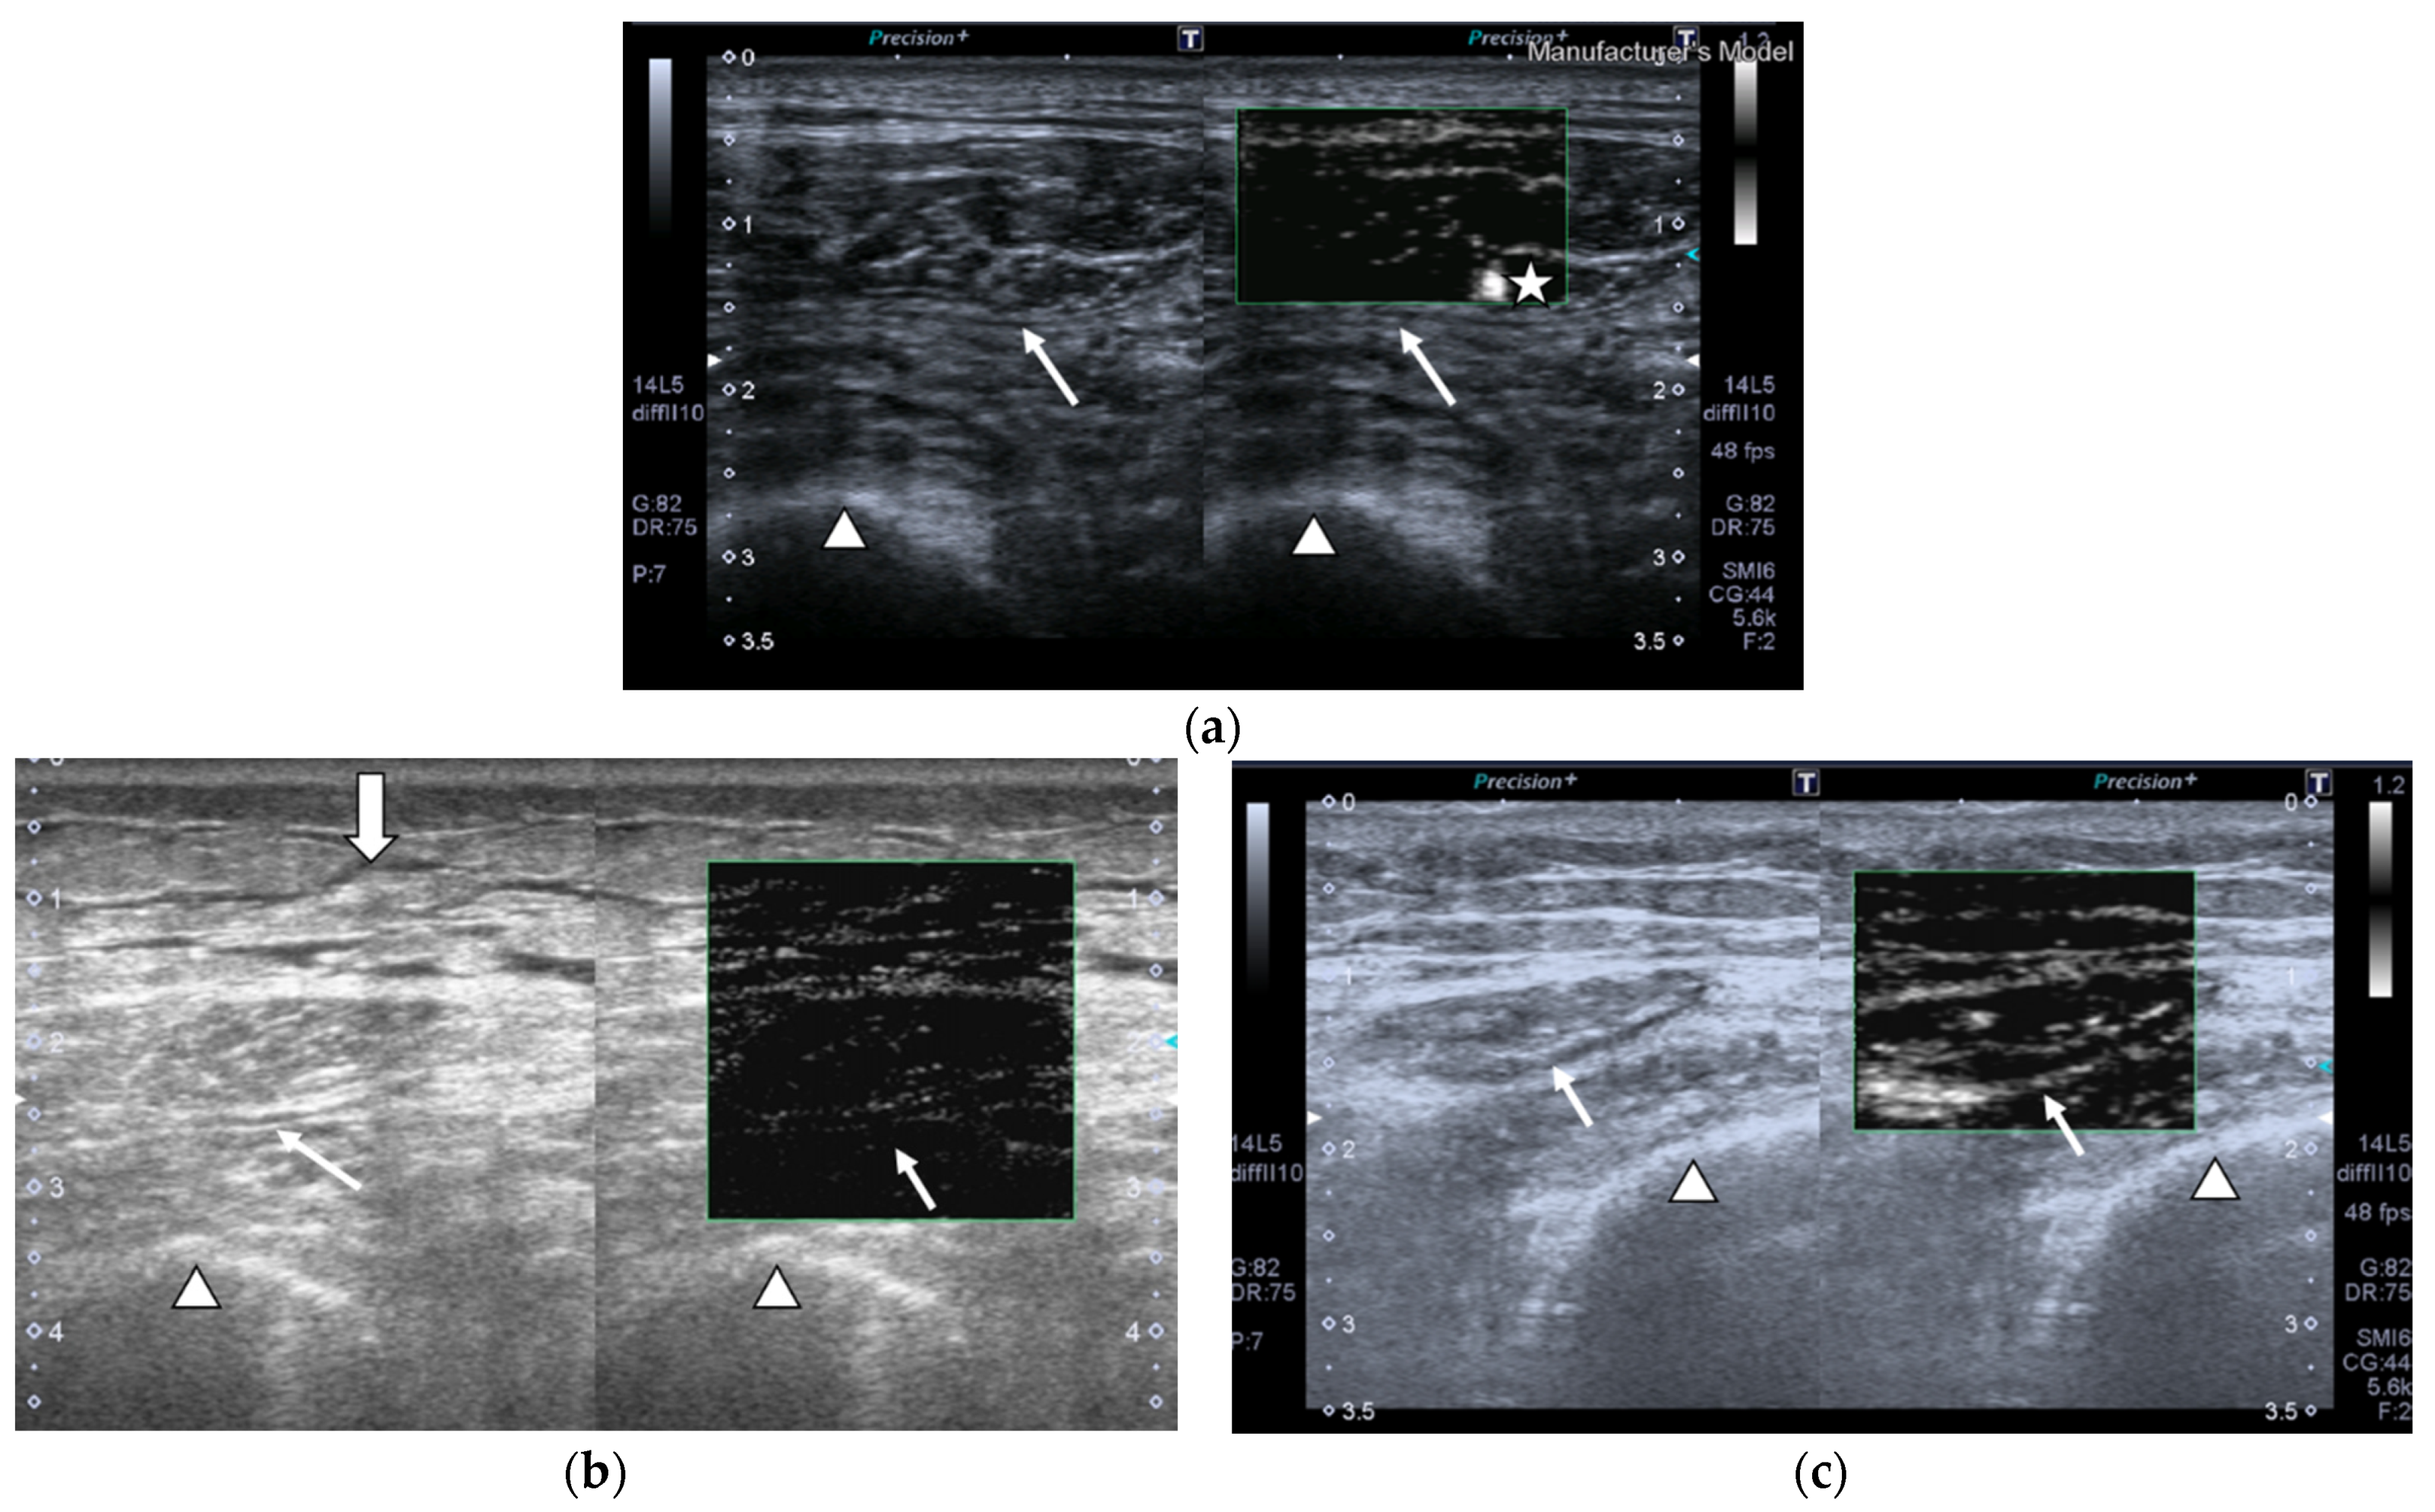

Images of the peak maximum and minimum CEUS intensity of a patient and a healthy control are shown in Figure 3 and Figure 4.

Figure 4.

Transversal QRF muscle of a patient with multiorgan failure (77 years old). (a). Transversal ultrasonography scan shows the QRF muscle (arrow) and vascularization after contrast-enhanced ultrasound (CEUS) administration (arrowhead). CEUS imaging and time–intensity curve analysis are shown using the built-in software. (b) ROI (pink circle) in the area of strongest enhancement indicates maximum perfusion in the QRF. (c) ROI (pink circle) in the area of lowest enhancement indicates minimum perfusion in the QRF.